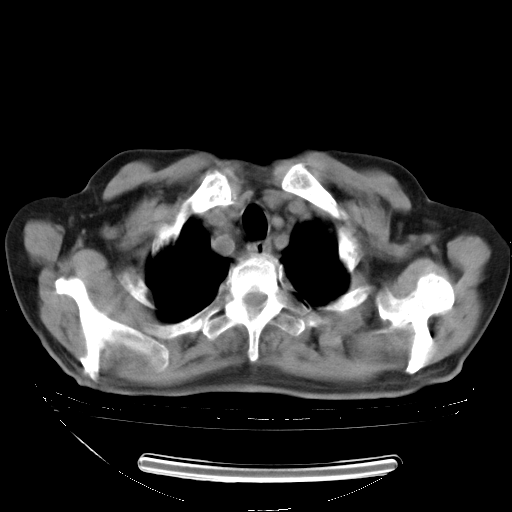

今天复查肺部CT,发现双肺广泛磨玻璃样改变。所以我把3月19日和5月9日相隔50天的肺部CT上传。请大家会诊。

2009年3月19日肺部CT片。

2009年3月19日肺部CT

大致读了系列胸部CT:纵隔窗无明显异常,肺窗:从4、27至今:主要是双肺中下野外带可见毛玻璃样改变,目前处于急性肺泡炎阶段,至于原因考虑1、结替组织或胶原血管性疾病所致?2、恶性疾病如恶组在肺部所致的表现或细支气管肺泡癌?3、药物或其它原因如肺蛋白沉着症所致肺泡炎目前不太可能?总之,明天就去请我院的呼吸科、感染科、血液科和临免专家会诊哈。